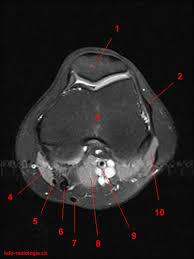

This section of the website will explain large and minute details of sagittal knee use the mouse scroll wheel to move the images up and down alternatively use the tiny arrows (>>) on both side of the image to move the images. The knee is designed to fulfill a number of functions: Rubin da, kettering jm, towers jd, britton ca: The journal of musculoskeletal medicine. Support the body in an upright position without the need for muscles to work. Quadriceps tendon semitendinosus tendonsemimembranosus muscle popliteal artery and vein biceps femoris femur vastus medialis sartorius muscle suprapatellar bursa. Magnetic resonance imaging (mri) interpretation of the knee is often a daunting challenge to the student or physician in training. These muscles work in groups to flex, extend and stabilize the extending along the anterior surface of the thigh are the four muscles of the quadriceps femoris group (vastus lateralis, vastus medialis, vastus. Find out more about the benefits of cbd via cbd clinicals. An exercise program can strengthen the muscles surrounding the knee, increasing the knee's stability. Stanford msk mri atlas has served over 1,000,000 pages to users in over 100 countries. Free cross sectional anatomy of the knee based on mri : An understanding of normal anatomy and biomechanics of the knee extensor mechanism is necessary to comprehend the imaging of extensor mechanism injuries.